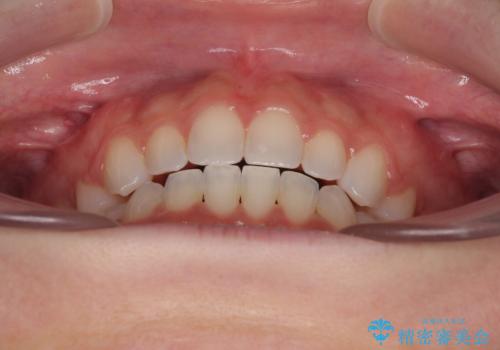

前歯のデコボコとクロスバイト ワイヤー装置での抜歯矯正

スペースを閉じるために期間を要しましたが、無事に綺麗な口元に仕上げることができました。